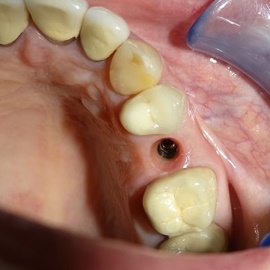

Przedtrzonowce często należą do okolicy estetycznej należy więc zwrócić wzmożona uwagę na poprawną anatomię tkanek kości i dziąsła. Po utracie zęba 25 pacjentka kilka lat chodziła bez jego uzupełnienia, doszło do przesunięcia się zęba 26. U tej pacjentki przed laty był wykonany most jednobrzeżny na czwórce, dość szybko doszło jednak do przeciążenia zęba filarowego, zaniku kości wyrostka i wreszcie pęknięcia korzenia zęba filarowego mostu. Po ekstrakcji i wygojeniu kości stwierdzono ubytek kości wyrostka przekraczający objętość 50% stanu początkowego. Stąd główny nacisk położono na odbudowę tkanek. Uzyskano zadowalający wynik anatomiczny.